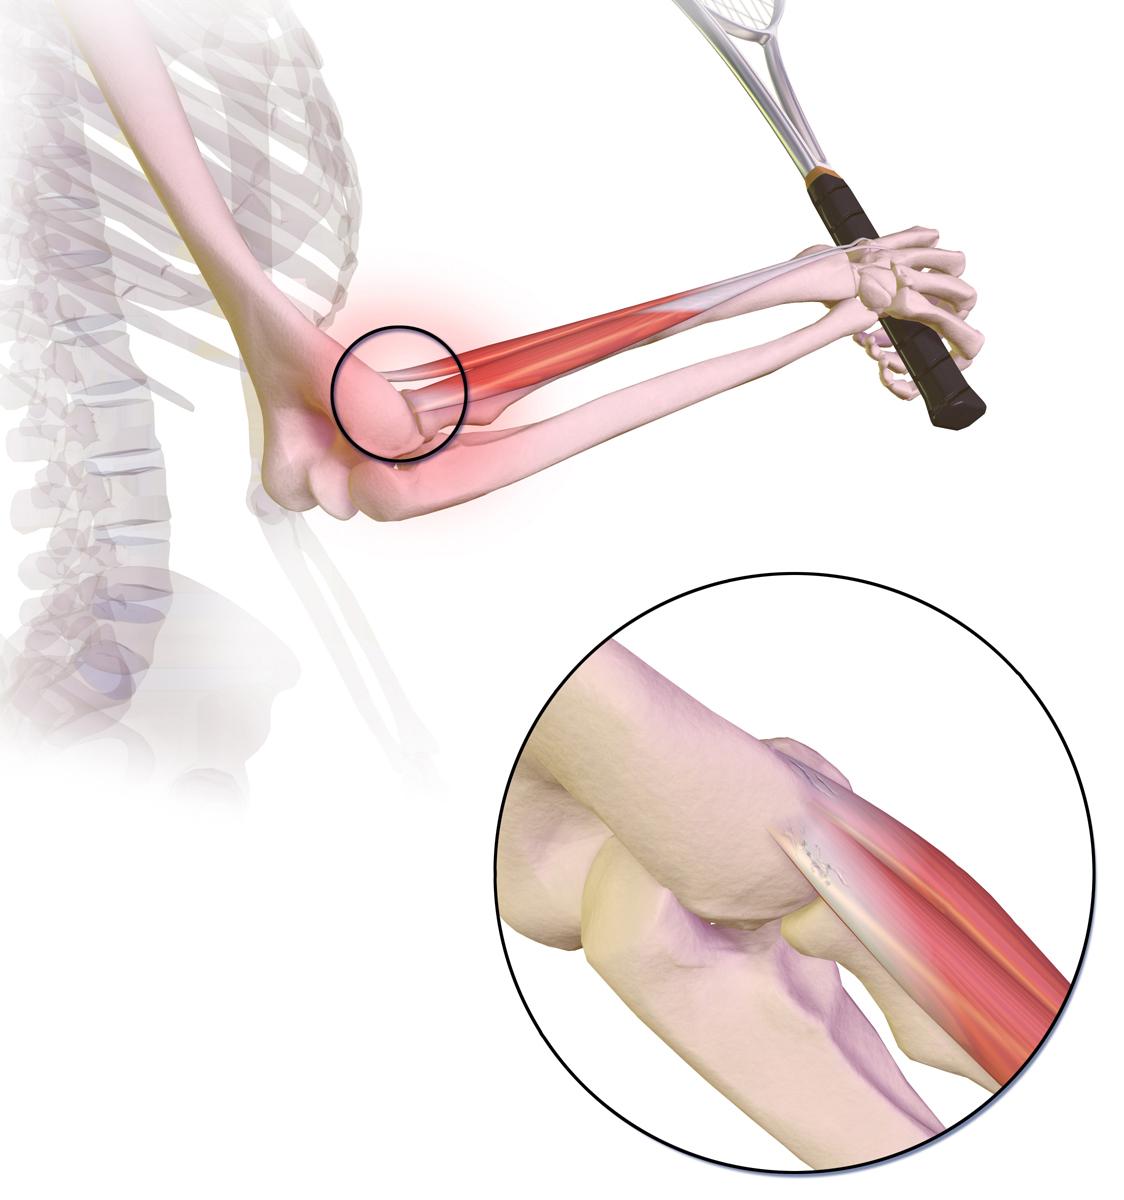

Tennisarm

Der Tennisarm(medizinischer Fachbegriff: laterale Epicondylitis) entsteht, wenn sich die Sehnen an der Außenseite des Ellenbogens entzünden und wund werden.

Dieses Bild zeigt, wo der Schmerz beim Tennisarm auf der Außenseite des Ellbogens auftritt:

Von BruceBlaus, CC BY-SA 4.0über Wikimedia Commons